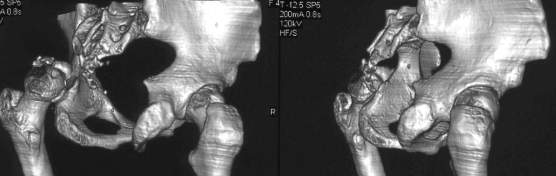

важаемые коллеги,пациент 23 лет (вес 75 кг), обратился к нам по поводу боли в тазобедренном суставе при ходьбе, нестабильность в нем при нагрузке. Ходит с тростью. 8 мес. назад попал в ДТП (никаких медицинских документов у него нет). Стоит ли открываться и вправлять вывих или сразу делать бесцементное тотальное эндопротезирование? С уважением, А. В. Вакуленко Клиника эндопротезирования суставов, г. ДонецкDear All, male patient 23 y.o., body weight 75 kg. Had RTA 8 months ago (medical records unavailable). Now has pain on motion in his left hip. On weight-bearing hip is unstable (patient use cane while walking). Keeping in mind his age, is it worth to perform open reduction? Or just do uncemented THR? Any comments are very welcome.

After 8 months, the hip will not easily come down into the acetabulum. It also appears to me that there is an impression fracture of the head of femur.

У нас в клинике, вероятно, выполнили бы открытое вправление в

2 этапа:низведение бедра аппаратом "таз-бедро", затем открытое

вправление. При развитии аваскулярного некроза в последующем

-эндопротезирование, в этом случае можно будет обойтись

обычной "press-fit" чашкой.

Здравствуйте. Позвольте поучаствовать в обсуждении. Поскольку пациент в течение 8 месяцев не получил адекватного лечения (видимо и по своей вине тоже), а также учитывая удовлетворительное состояние головки бедра(по данным КТ), есть смысл выполнить открытое вправление головки бедра с возможной фиксацией фрагмента заднего края пластиной. Далее начать восстановление функции сустава, дозированную нагрузку. Возможно молодой возраст пациента поможет ему отдалить время эндопротезирования. Желаю успехов.